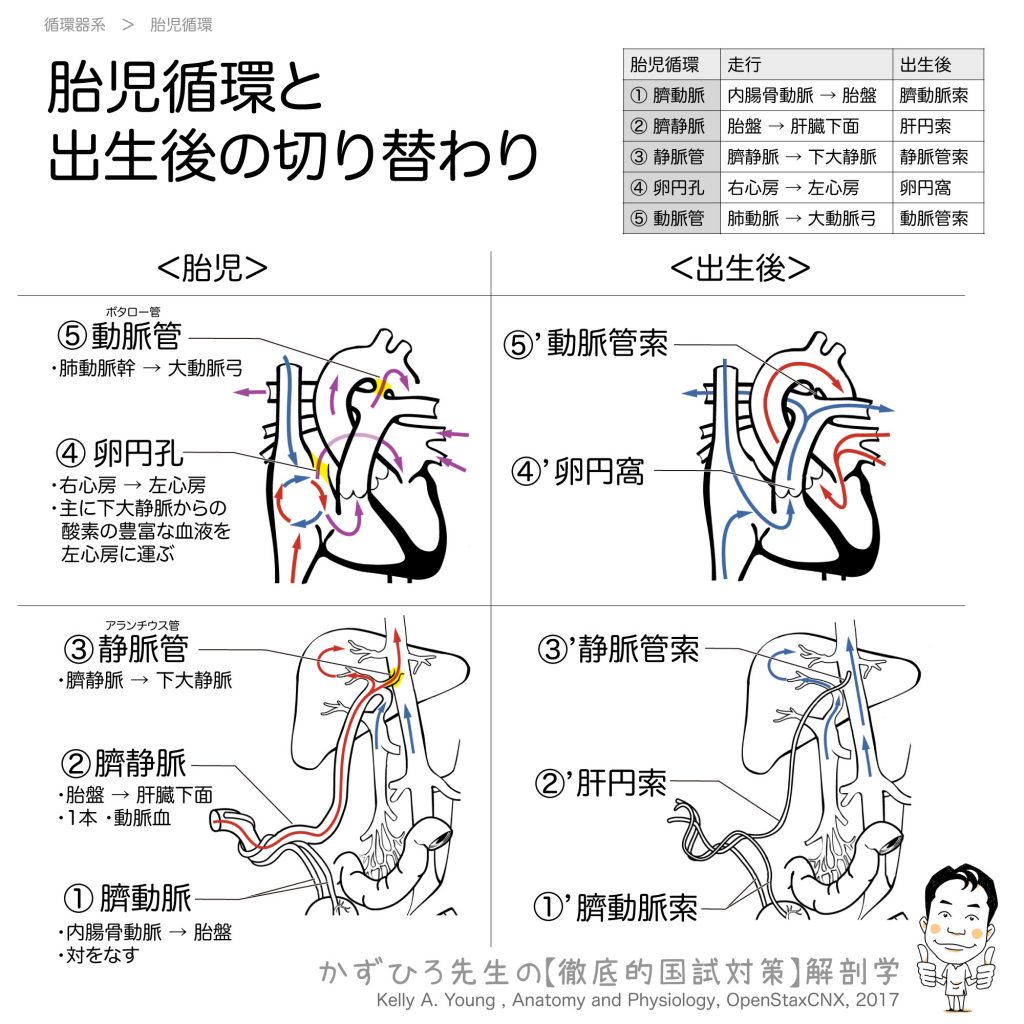

裁断済】マイヤース腹部放射線診断学 発生学的・解剖学的アプローチ。マイヤース腹部放射線診断学: 発生学的・解剖学的アプローチ。マイヤース腹部放射線診断学 発生学的・解剖学的アプローチ。mochi*°様✳︎ 小さなスコーンとポルポロン * スコーン 2月*。「マイヤース腹部放射線診断学 発生学的・解剖学的アプローチ」太田 光泰定価: ¥ 15400円+税即購入OKです(^^)・裁断済みです。書き込みはなく綺麗な状態です。裁断してある中古品であること、素人による裁断であることをご理解のうえ、ご購入下さい。神経質な方は購入をお控えください。・1-2日で発送致しますが、週末や連休中は発送が休み明けになることがあるかも知れません。。徹底的解剖学 | 黒澤一弘(かずひろ先生)による解剖生理学講座。綴じ口より裁断されておりバラバラの状態です。vol2 岩越真一先生(放射線医学 助教) | 奈良県立医科大学。グレイ解剖学 原著第5版 / Anatomy 今日も明日も/グレイ解剖学。裁断しているため、「傷や汚れあり」 にました。福井大学における革新的な画像医学教育への挑戦─ITとAiをベース。ポータブル電磁超音波探傷器 VOLTA2 (Innerspec Technologies。・ほとんど使用しておりませんが、多少のキズや小さな角折れ等あるかもしれません。黒澤一弘(かずひろ)解剖学IT教育・指圧師・ラダック on X。JRC2012 ziosoft/AMIN Seminar Report 超四次元画像。・梱包は丁寧に行うようにしておりますが、配送中の破損は保証できませんので、ご了承下さい。徹底的解剖学 | 黒澤一弘(かずひろ先生)による解剖生理学講座。画像診断を学ぼう 単純X線からCT・MRI・超音波まで 第2版。その際はご容赦下さい。【裁断済】小児・成育循環器学 改訂第2版